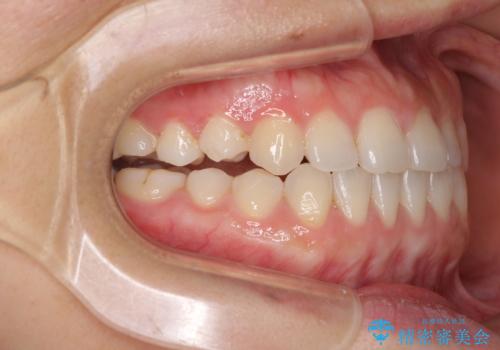

- 上下の前歯の隙間を気にして来院された患者様です。

インビザラインを用い、上下歯列のスペースを閉じていくこととしました。

治療期間中は奥歯がほとんど咬めない状態が続き、食事に大変苦労されました。

最終的には隙間もしっかりと閉じ、奥歯も咬みやすい状態でしあげることができました。